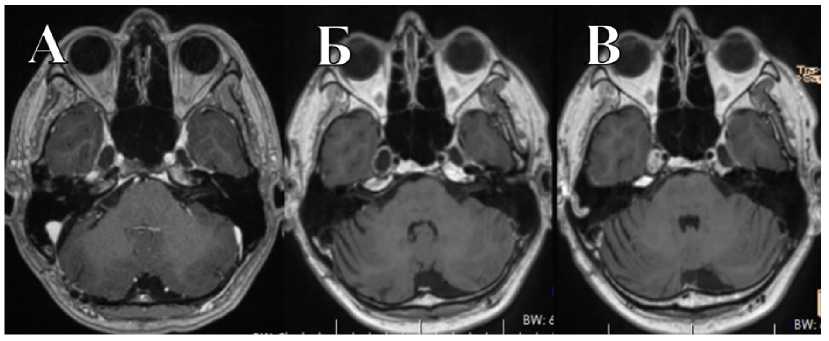

В НМИЦ нейрохирургии им. ак. Н.Н. Бурденко обратился пациент О., 33 лет. Развитие заболевания протекало в течение года в виде онемения в правой половине лица и болью в области внутреннего угла глаза. По данным МРТ, выявлена внемозговая опухоль средней и задней черепных ямок справа, накапливающая контрастное вещество, размеры узла в СЧЯ 1,2 × 1,25 × 1,4 см, в ЗЧЯ — 2,16 × 1,9 × 1,56 см (рис. 4). Объем опухоли в СЧЯ — 2,37 см3, в ЗЧЯ — 3,85 см3. При объективном обследовании перед операцией выявлены нарушения функции тройничного нерва справа в виде снижения роговичного рефлекса, а также горизонтальный нистагм.

Рис. 4. МРТ пациента О. до операции. Внемозговая опухоль СЧЯ и ЗЧЯ, накапливающая контрастное вещество

Fig. 4. MRI of patient O. before surgery. Extracerebral tumor of MCF and PCF with contrast enhancement

Через 6 мес. после операции пациенту проведено лучевое лечение на аппарате Кибер-нож в режиме радиохирургии. Разовая доза — 13,52 Гр, объем облученной опухоли составил 3,46 см3. На МРТ перед лучевой терапии визуализирован фрагмент невриномы тройничного узла в СЧЯ справа размерами 1,56 × 1,59 × 1,35 см, объем опухоли 2,46 см3 (рис. 6). В клинической картине на момент облучения сохранялась гипестезия и снижение роговичного рефлекса, однако через 3 мес. присоединились парестезии в лице и слабость жевательной и височной мышц на стороне операции.

Через 1 г. после лучевой терапии в клинической картине пациент отмечает частичное восстановление чувствительности на лице, а также появление недостаточности VIII черепного нерва справа. Контрольная МРТ продемонстрировала уменьшение опухоли, размеры — 1 × 1,88 × 0,74 см, объем — 0,73 см3 (рис. 6).

Рис. 6. МРТ пациента О.: А — перед лучевой терапией: невринома в СЧЯ, опухоль в ЗЧЯ удалена тотально; Б — через 6 мес. после лучевой терапии: небольшой остаток опухоли в СЧЯ; В — через 1 г. после лучевой терапии: небольшой остаток опухоли в СЧЯ

Fig. 6. MRI of patient O.: A — before radiation therapy: neuroma in MCF, tumor in PCF completely removed; Б — 6 months after radiation therapy: small tumor remnant in MCF; В — 1 year after radiation therapy: small tumor remnant in MCF